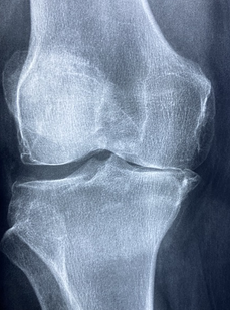

무릎 염증의 원인은 다양합니다. 가장 흔한 원인은 관절염입니다. 관절염은 연골이 마모되거나 손상되어 뼈가 서로 마찰되는 상태를 말합니다. 연골은 무릎 관절의 세 개의 뼈 사이에 있는 매끄러운 조직으로, 관절의 움직임을 부드럽게 하고 충격을 흡수하는 역할을 합니다. 연골이 없어지면 관절에 염증이 생기고 통증이 발생합니다. 관절염에는 골관절염, 외상 후 관절염, 류마티스 관절염 등이 있습니다 .